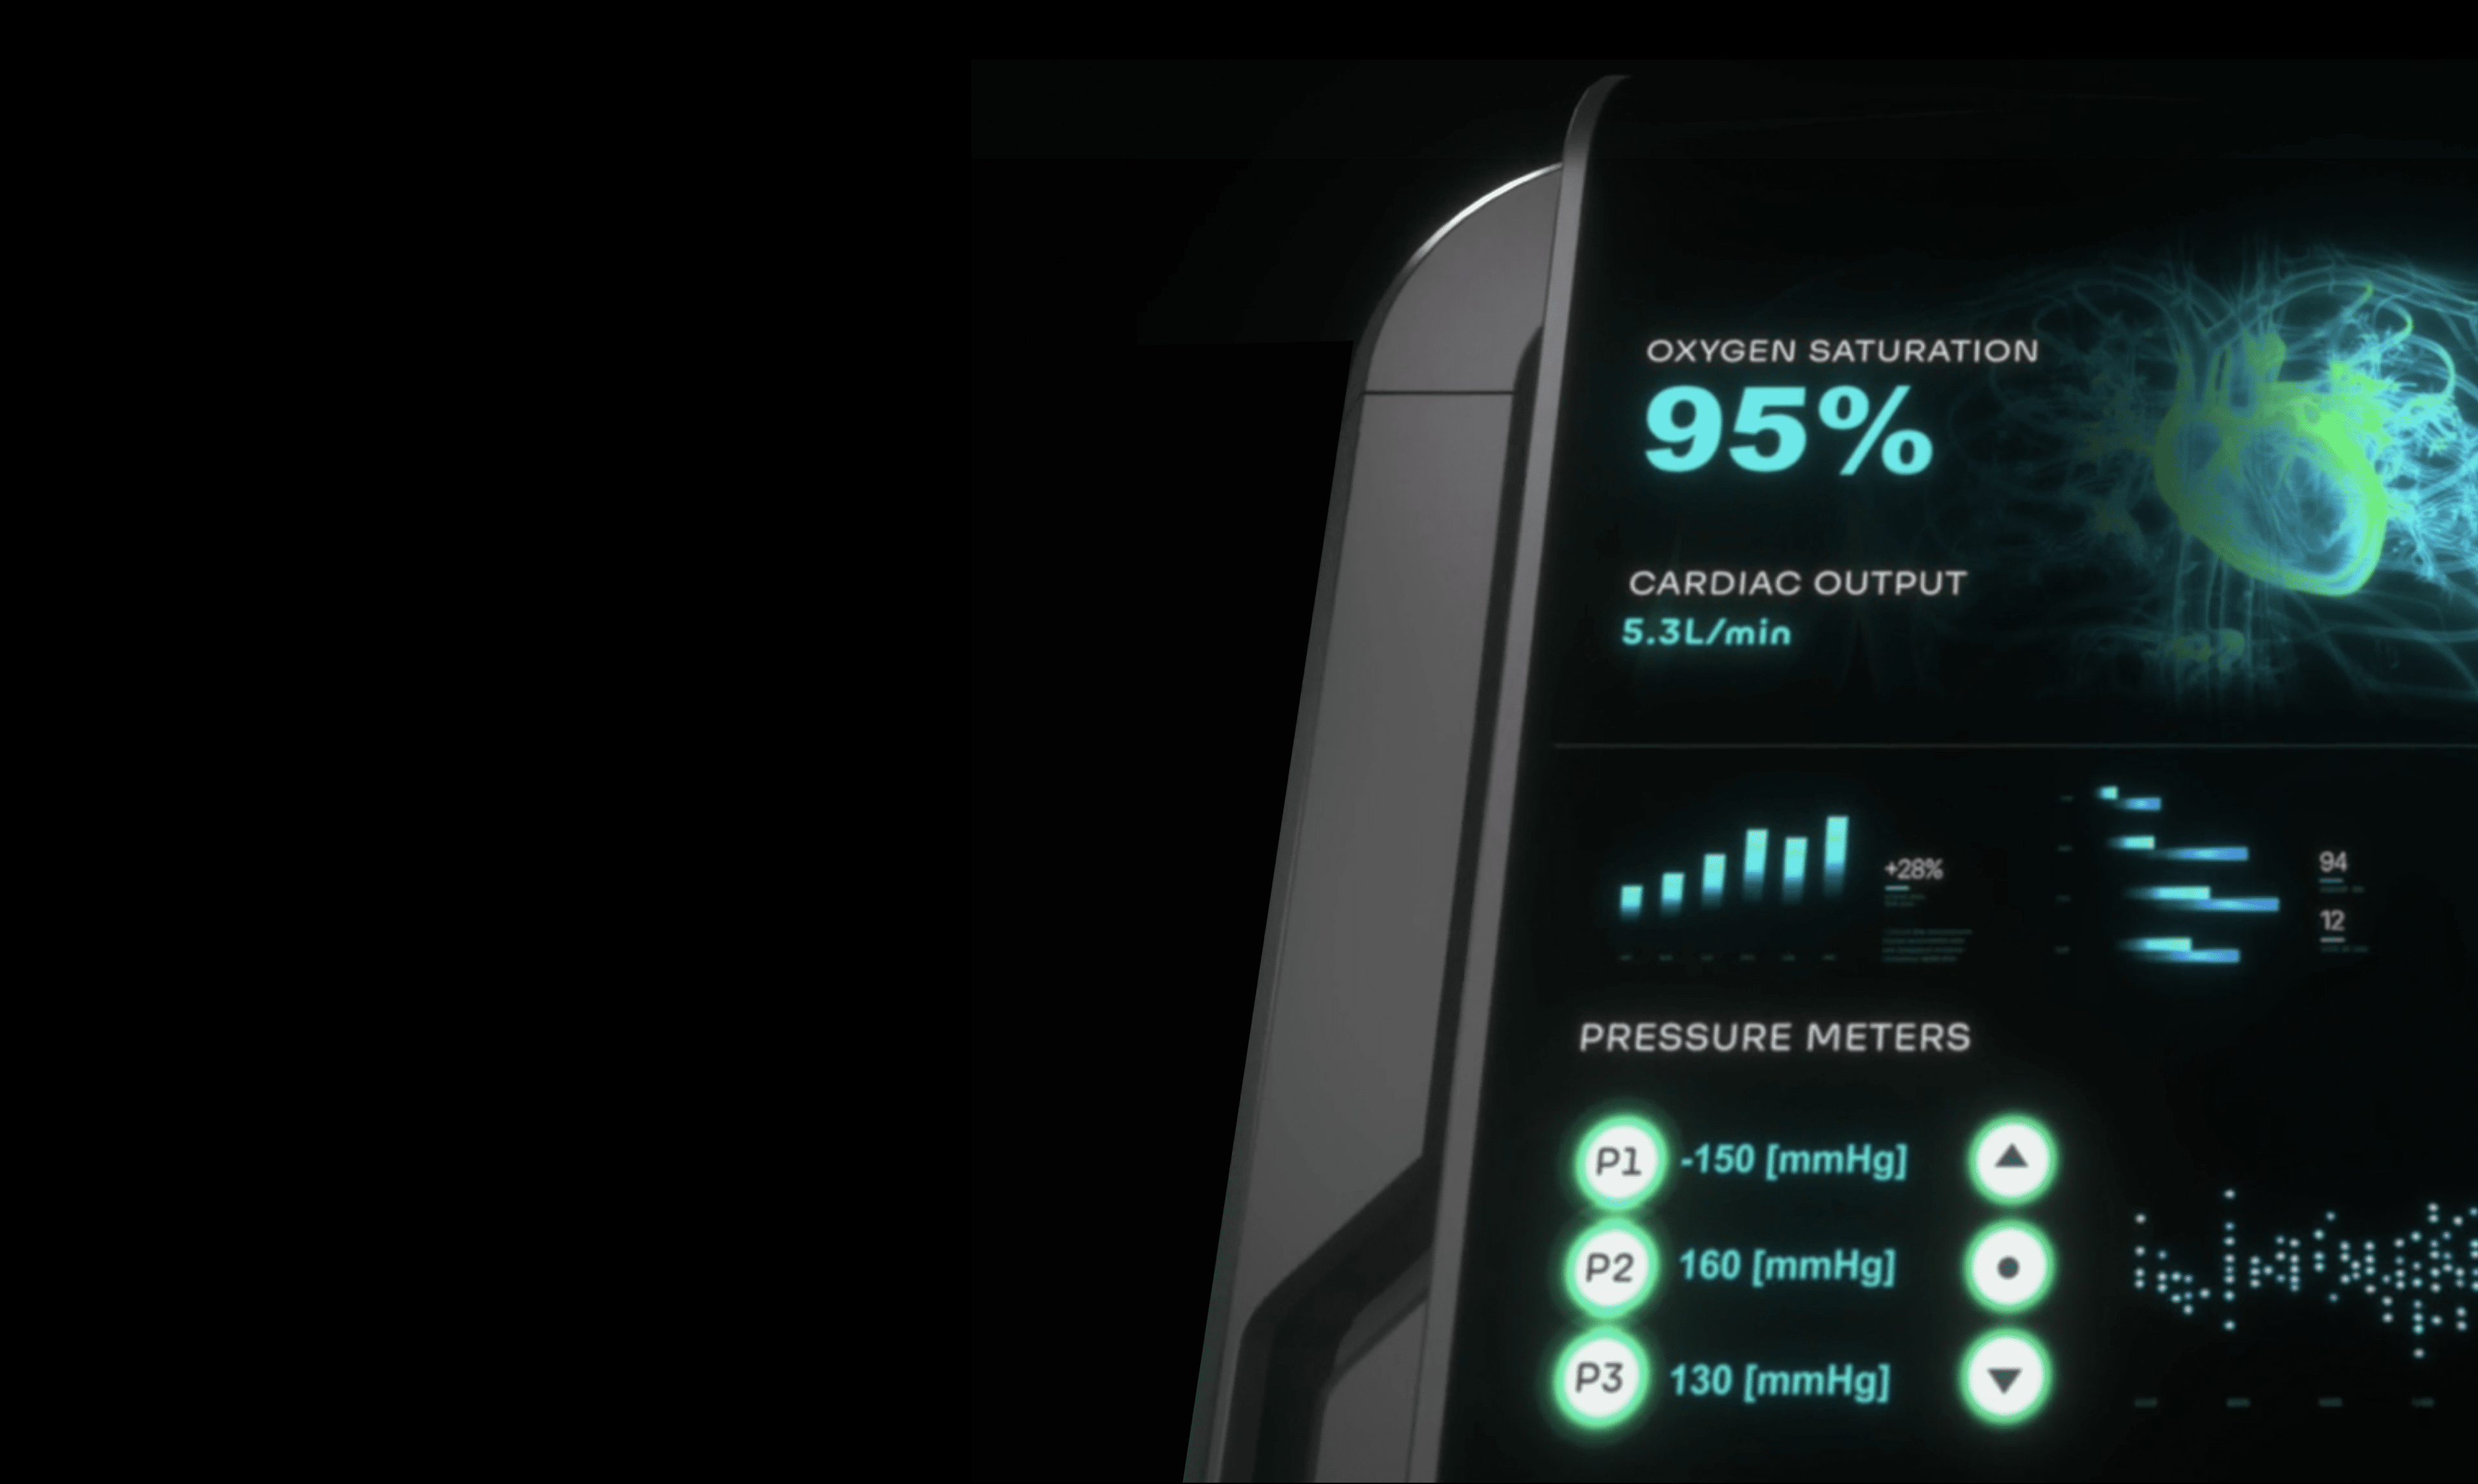

Blood parameters measured continuously and in real-time

Early detection of changes · Provides decision-making

assistance data

The adaptive technology is designed to continuously monitor the patient's blood parameters in real-time, enriching small volumes of blood with oxygen and simultaneously removing carbon dioxide.

HYLA™ Clip-On Blood Lab

Without the need to take intermittent blood samples, the HYLA™ Optic Blood Lab is designed to test, monitor and alert of sudden changes in key blood parameters.

The HYLA™ Blood Sensor is designed to perform real-time analyzing of blood gases, for patients undergoing medical procedures or requiring more frequent patient monitoring.